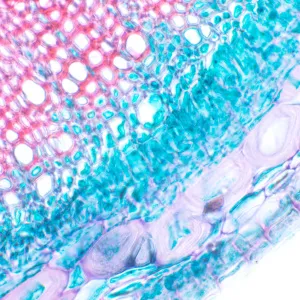

MAGUS Bio 230T – биологический тринокулярный микроскоп для лабораторных и исследовательских наблюдений в медицине, фармацевтике, криминалистике, биотехнологии и других областях науки. Применяется для работы с плоскими полупрозрачными и прозрачными образцами биологического происхождения: тонкими срезами и мазками. Оснащен ахроматической оптикой и галогенной подсветкой, наблюдения ведутся в проходящем свете в светлом поле. Микроскоп рассчитан на установку дополнительных аксессуаров для использования большего количества методов наблюдений: темного поля, фазового контраста, поляризованного света.

Чтобы расширить возможности микроскопа MAGUS Bio 230T, достаточно дооснастить его аксессуарами. Доступны окуляры и объективы, цифровые камеры и калибровочные слайды, конденсоры темного поля, устройства для наблюдений в поляризованном свете и с использованием фазово-контрастной микроскопии.